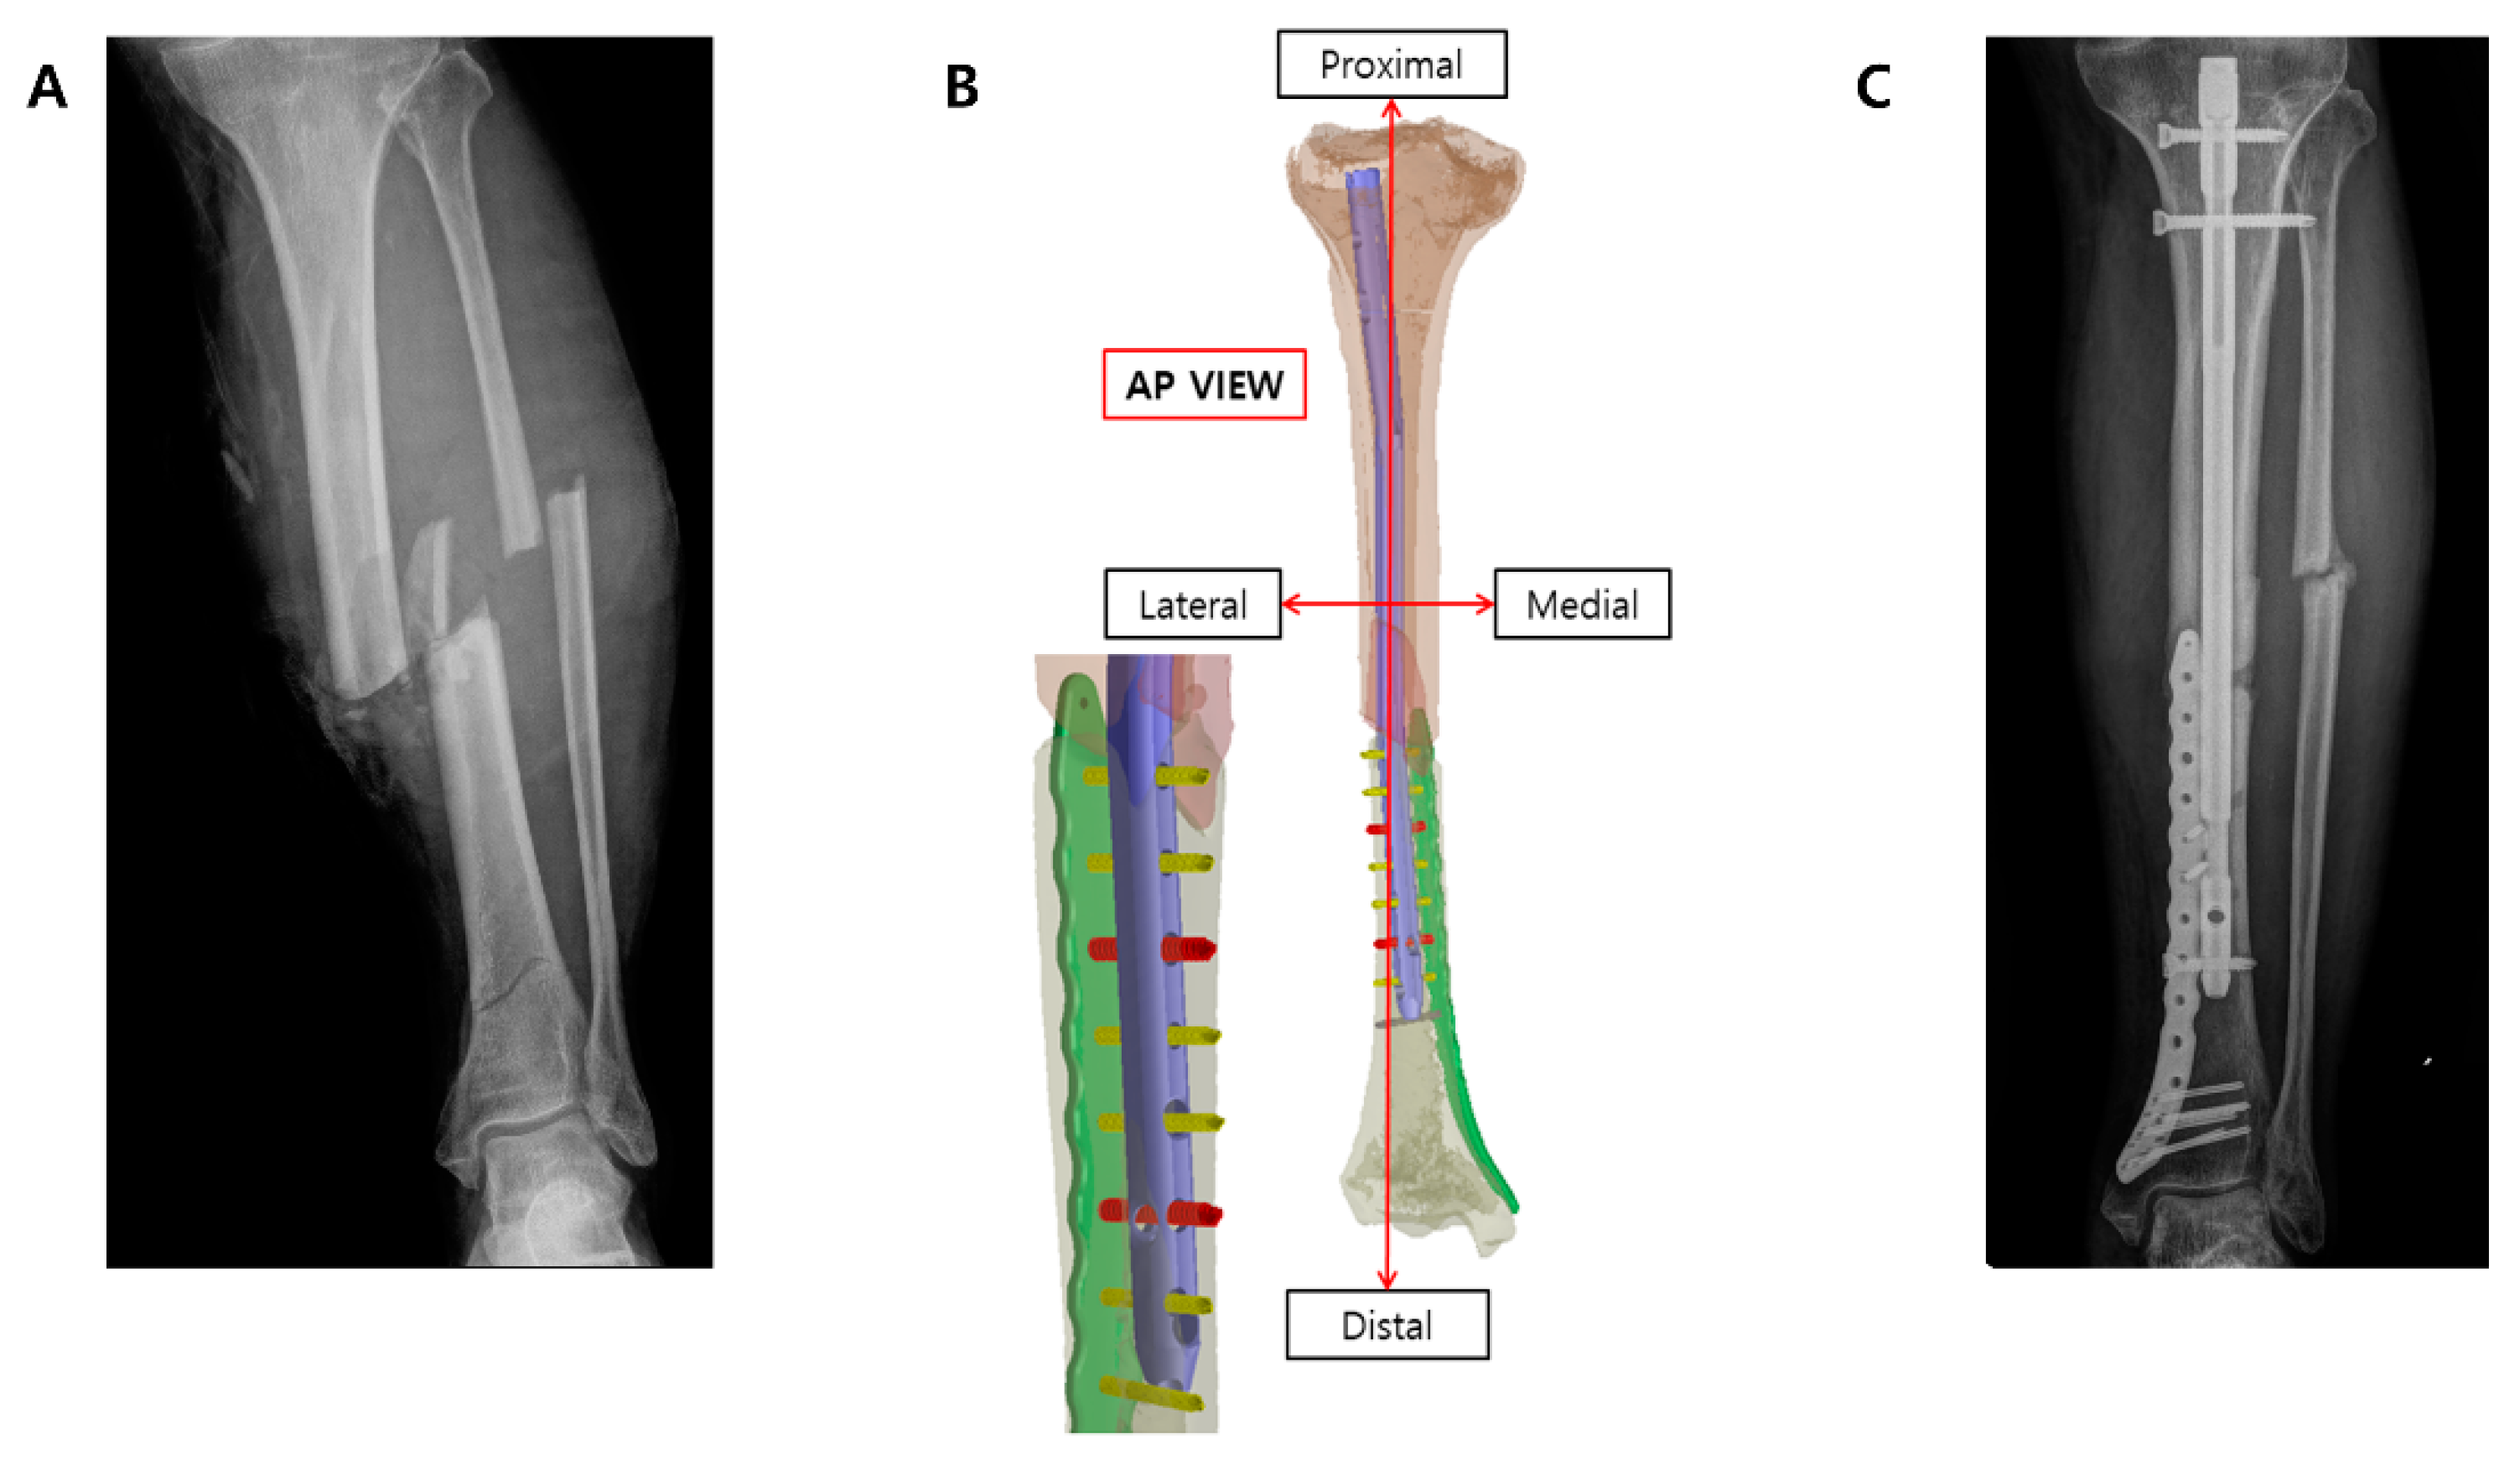

Ten tibial fractures that underwent surgical reduction were followed up for 1–2 years. Over the follow-up period, in nine out of 10 tibiae, the fracture plate remained undamaged, deformed, and securely fixed within the body. The mean American Orthopedic Foot and Ankle Society (AOFAS) score was 81.3 (SD 5.7). In one patient, who experienced failed fracture healing and had neurofibromatosis type 1, the fracture plate did not fulfill its intended role in the case of an open fracture. Consequently, revision surgery was performed using a tibial intramedullary nail and additional bone grafting. A biopsy of the previously failed fracture site revealed chronic inflammation with fibrosis and dead bone particles (Figure 4).

Figure 4.

Failed fracture plate case: A 59-year-old female pedestrian was diagnosed with an open tibiofibular shaft fracture and subdural hematoma (SDH) following a traffic accident in which she was hit by a taxi. The patient had a medical history of neurofibromatosis. After massive irrigation and confirmed wound stabilization, minimally invasive percutaneous plating (MIPO) using a 3D-printed plate was performed 4 days after the trauma. The wound healed well without an additional coverage operation. Partial weight bearing was initiated 6 weeks post-operation. Three months post-operation, the patient presented to the outpatient clinic with lower leg pain; a plain radiograph confirmed plate breakage. She subsequently underwent reoperation with plate removal and conversion to an intramedullary (IM) nail fixation. An intraoperative biopsy of the nonunion site revealed findings consistent with chronic inflammation with fibrosis and the presence of dead bone fragments. After tibia IM nail fixation, fracture union was achieved, and the patient’s AOFAS score was 70. R means right sided.